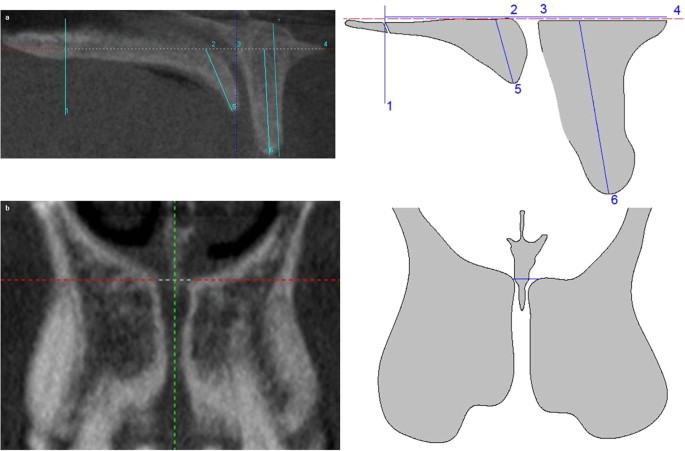

Level 3

It is located by moving the horizontal line to the foramina of Stenson on sagittal plane. In coronal slice the following measurement was taken on the horizontal line: (1) NC diameter at level 3 (CD3) (Fig. 3).

In sagittal slice the following measurements are taken on the horizontal line: (1) PBP width at level 3 (PW3), (2) the width from the most posterior point of the transverse palatine suture to the palatal wall of NC, (3) NC sagittal diameter at level 3 (SD3) and (4) PBP width at level 3 (PW3). In addition, the following measurements are taken from the horizontal line to the inferior edges of BBP and PBP: (1) BBP length at level 3 (BL3). (2) PBP length at level 3 (PL3), and, (3) the total BBP length (tBL) was also calculated by joining midpoints of coronal and apical BBP width (Fig. 3).